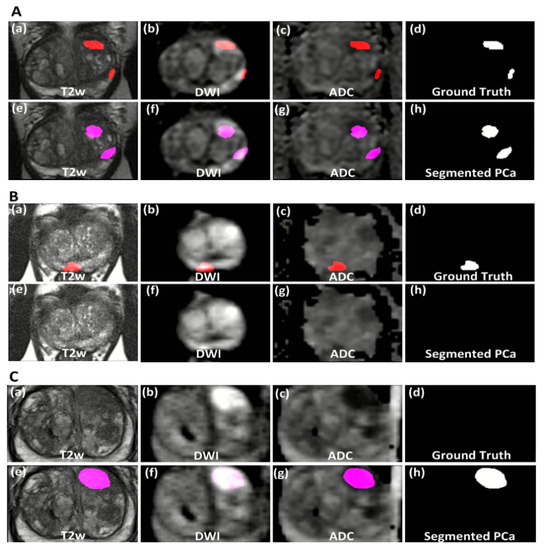

3. Results